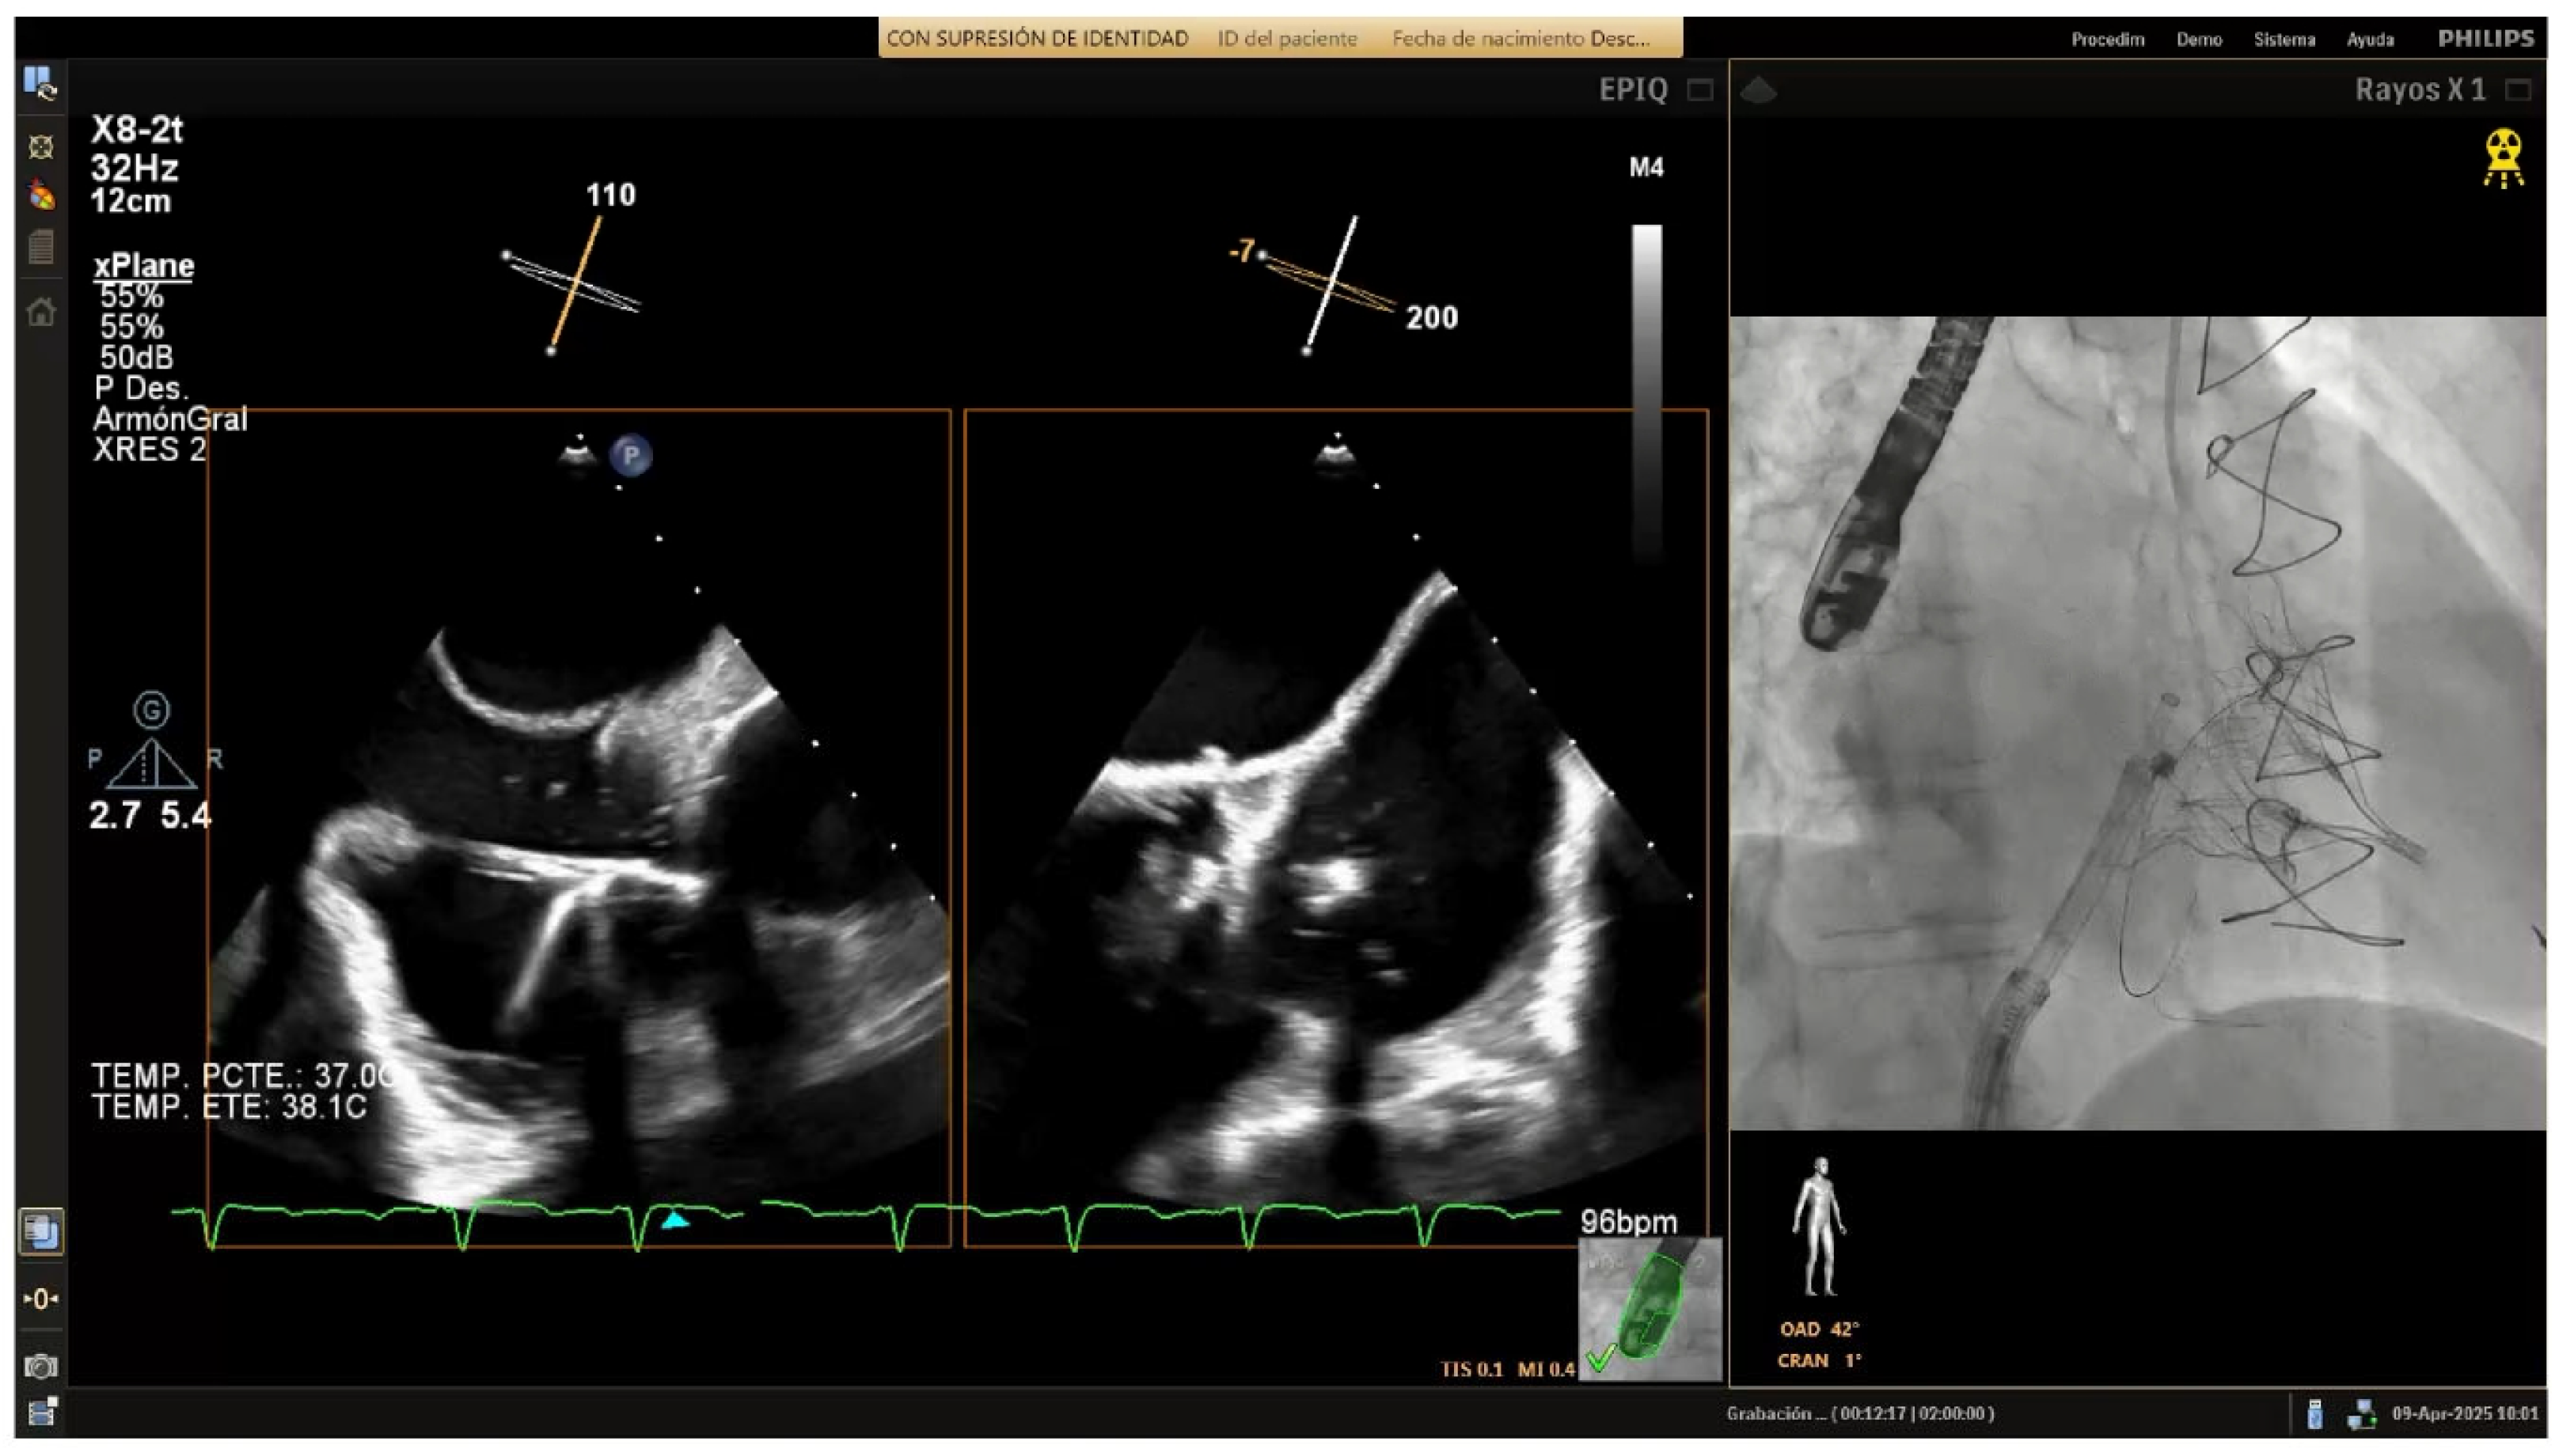

4.3.4. Posterior Annulus (Hooking)

Anchoring along the posterior annulus (

Figure 6A) poses unique challenges due to its parallel alignment with the echo beam and distance from the probe. At this point, the device often needs to be curved in an angle of 90° between the IC and the TSS (“hooking”) to cross the RCA and properly reach the anchor points (

Supplemental Video S2). A mid-esophageal MPR view and a transgastric view at 150° provide a better view of this segment. RAO and LAO projections are employed to verify the alignment of the IC with the annulus and ensure there is no contact with unintended structures [

10,

11]. If loss of coaxiality or echo shadowing occurs, corrective actions include sheath repositioning, modification of LAO/RAO angles, or pre-shaping of the catheter curve.

4.3.5. Posteroseptal Commissure

Finally, as the band approaches the posteroseptal commissure (

Figure 6B), deep esophageal and mid-esophageal bicaval views ranging from 0° to 135° may facilitate visualization of the coronary sinus and the septum, which are critical during this phase [

11]. For final anchors placement, the RAO view helps confirming anchor security and alignment with the valve annulus, while avoiding any potential misalignment or overlap with other structures. Biplane imaging enhances alignment checks and reduces shadowing artifacts.

Figure 6.

Posterior tricuspid annulus anchoring. (A) Posterior annulus anchoring requires navigating anatomical complexity due to echo beam alignment and distance from the probe. A 90° “hooking” angle between the implant catheter and the transvenous steerable sheath is often necessary to overcome the right coronary artery and access the posterior annular region. Transgastric transesophageal view (150°) and upper esophageal retroflexed views aid visualization, while RAO and LAO fluoroscopic projections confirm alignment and proper catheter trajectory. (B) Final anchoring at the posteroseptal commissure using deep and mid-esophageal bicaval views (0–135°) for visualization of the coronary sinus and septum. RAO projection and biplane imaging help verifying proper anchor placement and avoiding overlap or misalignment with nearby structures.